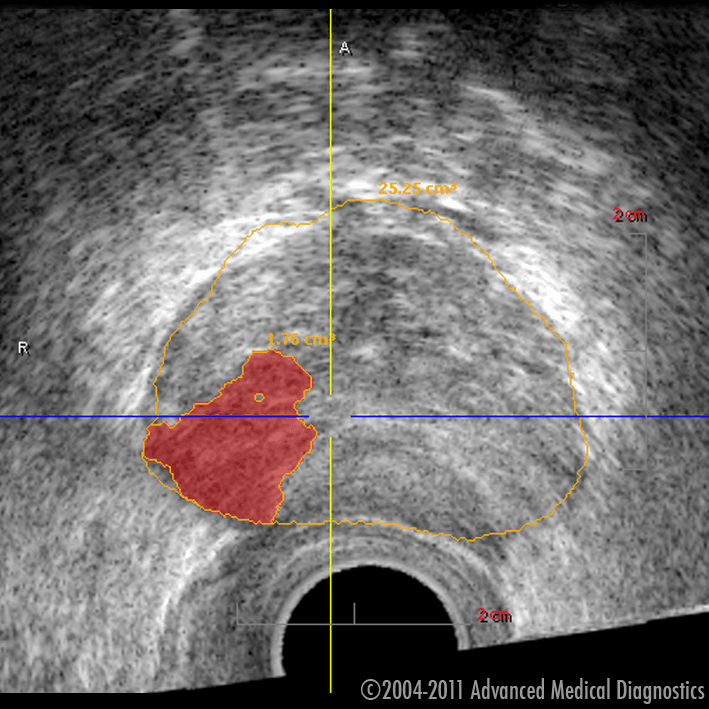

Ar 3D histoskeneri var „ieraudzīt” prostatas vēzi

ntz.lv1